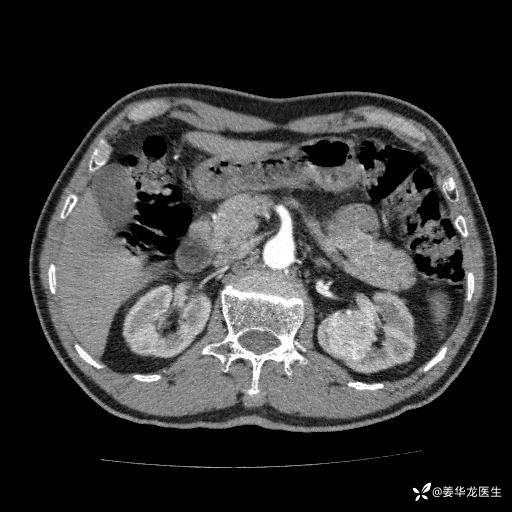

左肾中心型肾门部肿瘤39mm×34mm×36mm,右肾GFR25ml/min,部分切还是全切?

患者75岁老年男性,体重50kg,无高血压、肾病、糖尿病等基础病,检查发现左肾中心型肾门部肿瘤,右肾GFR只有25ml,无肉眼血尿,无镜下血尿。入院验血常规检查均正常,包括肾功能,肌酐102.7umol/L.

二、左肾肿瘤与左肾集合系、左肾动静脉关系密切,左肾部分切除术可行吗?成功率有多大?成功部分切后,肾功能还有多少?